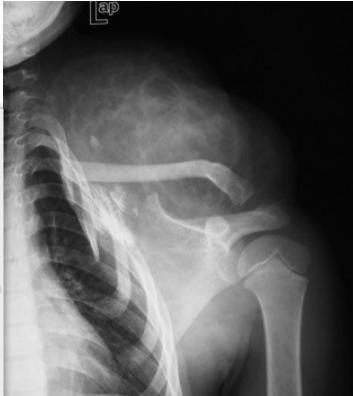

X-rays

- Which bone, and which site in bone?

- Solitary or multiple?

- Bone forming or bone eating?

- Margins: well-defined or ill-defined?

- Calcifications in the lesion?

- Is cortex eroded or destroyed?

- Is there periosteal new bone formation?

- Soft tissue extension?